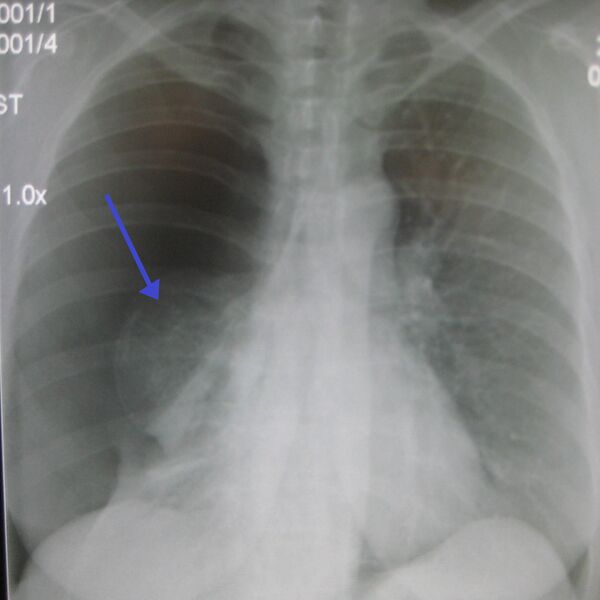

- Для подтверждения диагноза необходимо проведение рентгенографии грудной клетки (оптимальная проекция — переднезадняя, при вертикальном положении больного).

- Рентгенографическим признаком пневмоторакса является визуализация тонкой линии висцеральной плевры (менее 1 мм), отделённой от грудной клетки.

- Частой находкой при пневмотораксе является смещение тени средостения в противоположную сторону. Так как средостение не является фиксированной структурой, то даже небольшой пневмоторакс может вести к смещению сердца, трахеи и других элементов средостения, поэтому контралатеральный сдвиг средостения не является признаком напряжённого пневмоторакса.

- Смещение органов средостения в противоположную сторону должно оцениваться в соответствии с укладкой больного. При развороте в ту или иную сторону будет нарушена симметричность положения поперечных и остистых отростков грудных позвонков и их соотношения с грудинным концом ключиц. Ложное смещение средостения часто связано с разворотами. Истинное смещение средостения (симметричная укладка, а средостение смещено) при пневмотораксе свидетельствует о достаточном напряжении в нем, что является показанием к срочному дренированию плевральной полости. Смертельно опасный напряжённый пневмоторакс при закрытой травме грудной клетки, как правило, протекает с частичным коллапсом лёгких и смещением средостения[4].